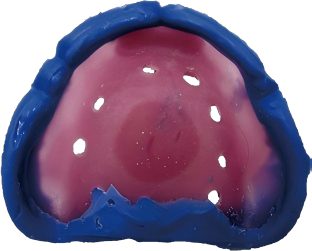

STEP 1: Make the individual tray

A custom tray helps control material thickness and ensures better fit accuracy.

Recommended Product:

HUGE Light Curing Tray

STEP 2: Perform Border Molding

Key step to enhance denture retention.

PERFIT Tray Adhesive in Border Molding

PERFIT Heavy Body in Border Molding